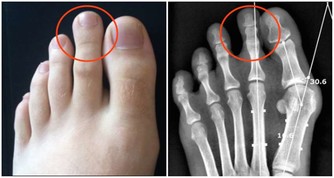

這些脂肪酸被稱為“必需脂肪酸”,因為您的身體無法製造它們。它們對您的眼睛,大腦和精子細胞很重要。它們還可以幫助預防與年齡有關的疾病,例如老年癡呆症,關節炎和黃斑變性,這些疾病可能導致失明。從脂肪魚,核桃,低芥酸菜籽油或亞麻籽等食物中能獲取。